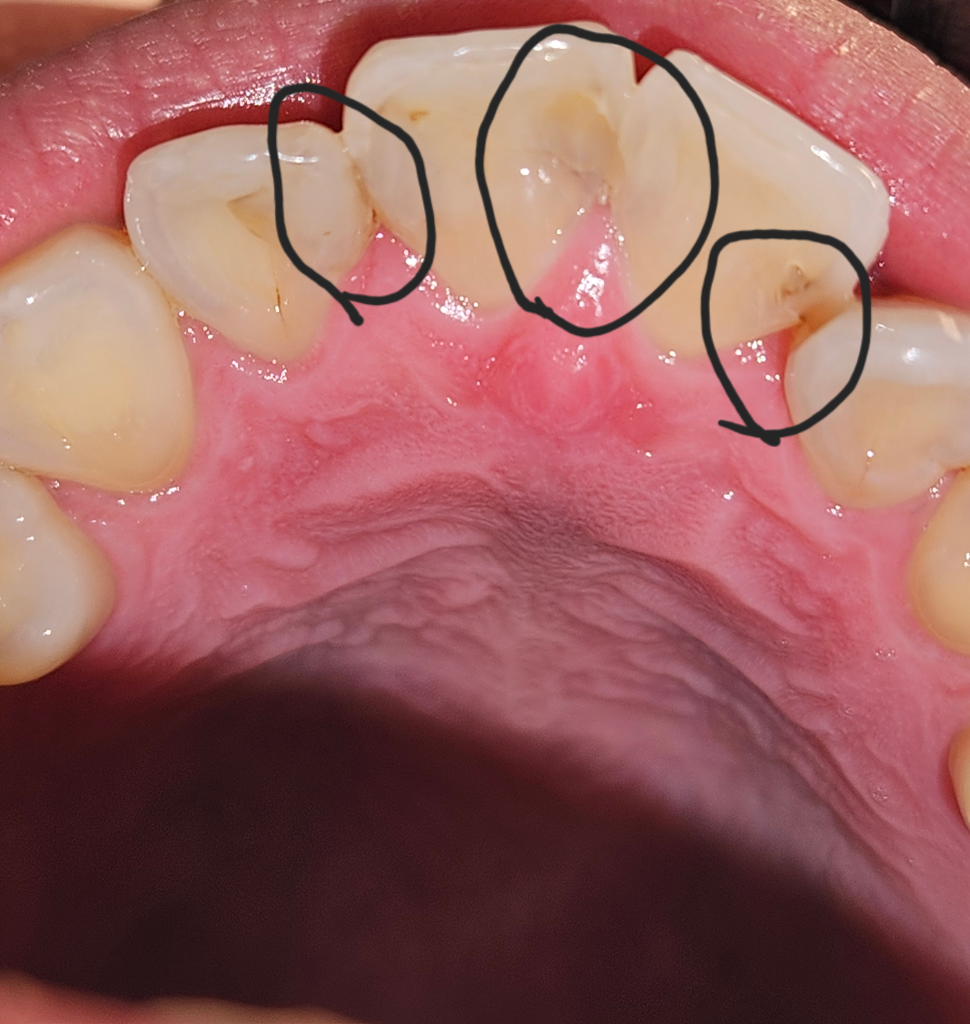

레진 충치 치료를 이렇게 치아 끼리 연결해 때우는게 맞나요?

치실도 안들어가게 두개를 연결해서 때워져있고

한쪽은 보면 레진이 다 채워져 있는거 같지도 않아요

이거 정상인가요?

따로 치아끼리 연결한다고 안내 받은적도 없고

치료 끝난 후 두텁게해서 뭐가 끼인 느낌 든다는 안내만 받았어요

지금 느낌은 치아 3개를 실로 묶어놓은 기분입니다.

• 2번 째 사진